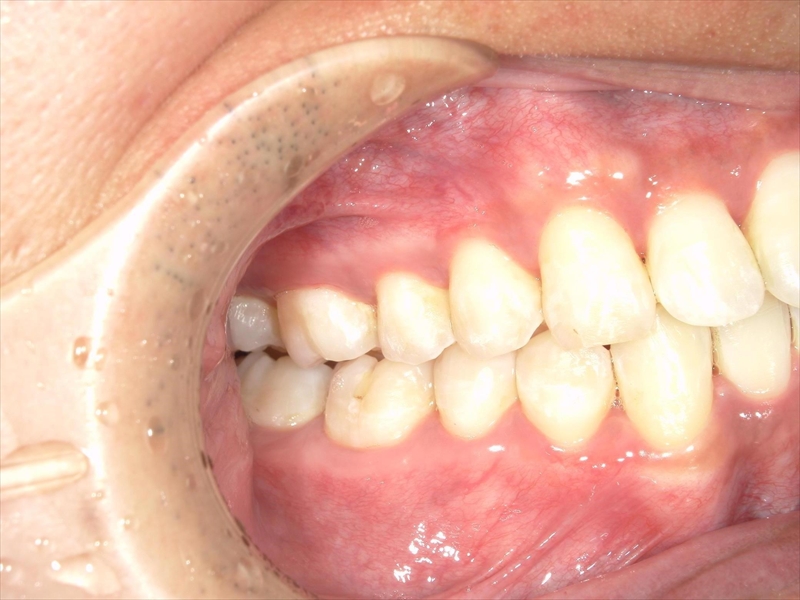

- 上あごの前歯がV字状の出っ歯

- 上あごに対して下あごがかなり小さい(過蓋咬合)

前歯のねじれ(V字)と出っ歯を下げるスペースを確保のため、両側1~5番目を0.2~0.5ミリ(計4ミリ)削ることと、奥歯から順に奥へ下げながら外側へ広げる計画を立案しました。